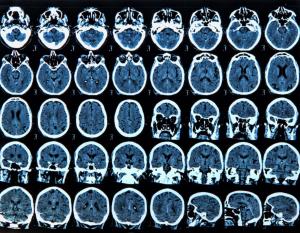

Un om de știință din Japonia a dezvoltat o tehnică care utilizează scanări cerebrale și inteligență artificială pentru a transforma imaginile mentale ale unei persoane în propoziții descriptive precise. Deși s-au înregistrat progrese în utilizarea scanărilor activității creierului pentru a traduce cuvintele pe care le gândim în text, transformarea imaginilor mentale complexe în limbaj s-a dovedit a fi o provocare, potrivit lui Tomoyasu Horikawa.

Cu toate acestea, noua metodă a lui Horikawa, cunoscută sub numele de „mind-captioning" (nr. subtitrarea gândurilor), funcționează utilizând inteligența artificială pentru a genera text descriptiv care reflectă informațiile din creier despre detalii vizuale, cum ar fi obiecte, locuri, acțiuni și evenimente, precum și relațiile dintre acestea. Horikawa, cercetător la Laboratoarele de Științe ale Comunicării ale companiei de telecomunicații NTT, situate în apropiere de Tokyo, a început prin a analiza activitatea cerebrală a patru bărbați și două femei, vorbitori nativi de japoneză cu vârste cuprinse între 22 și 37 de ani, scanându-le creierul în timp ce aceștia vizionau clipuri video.

Participanții au vizionat 2.180 de videoclipuri fără sunet, cu o durată de câteva secunde și cu conținut variat, incluzând obiecte, scene și acțiuni. Modele lingvistice de mari dimensiuni - sisteme generative de inteligență artificială antrenate pe seturi de date de mari dimensiuni - au preluat subtitrările clipurilor video și le-au transformat în secvențe de numere. Horikawa a antrenat modele separate și mai simple de inteligență artificială, cunoscute sub numele de „decodoare", pentru a corela activitatea cerebrală scanată legată de clipurile video cu secvențele numerice.

Apoi a folosit decodoarele pentru a interpreta activitatea cerebrală a participanților la studiu în timp ce aceștia vizionau sau își aminteau videoclipuri pe care inteligență artificială nu le întâlnise în timpul procesului de antrenare. A fost creat un alt algoritm pentru a genera progresiv secvențe de cuvinte care se potriveau cel mai bine cu activitatea cerebrală decodată. Pe măsură ce inteligență artificială a învățat din date, instrumentul de text descriptiv a devenit din ce în ce mai bun în utilizarea scanărilor cerebrale pentru a descrie videoclipurile pe care participanții le-au vizionat.